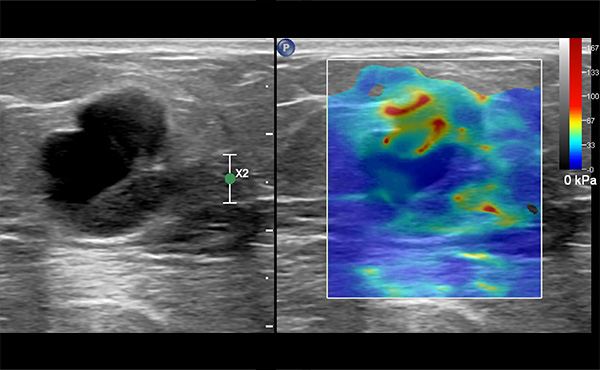

영상 검사에서 이상이 발견될 경우,

양성 종양인지 유방암인지 확진하기 위한 검사입니다.